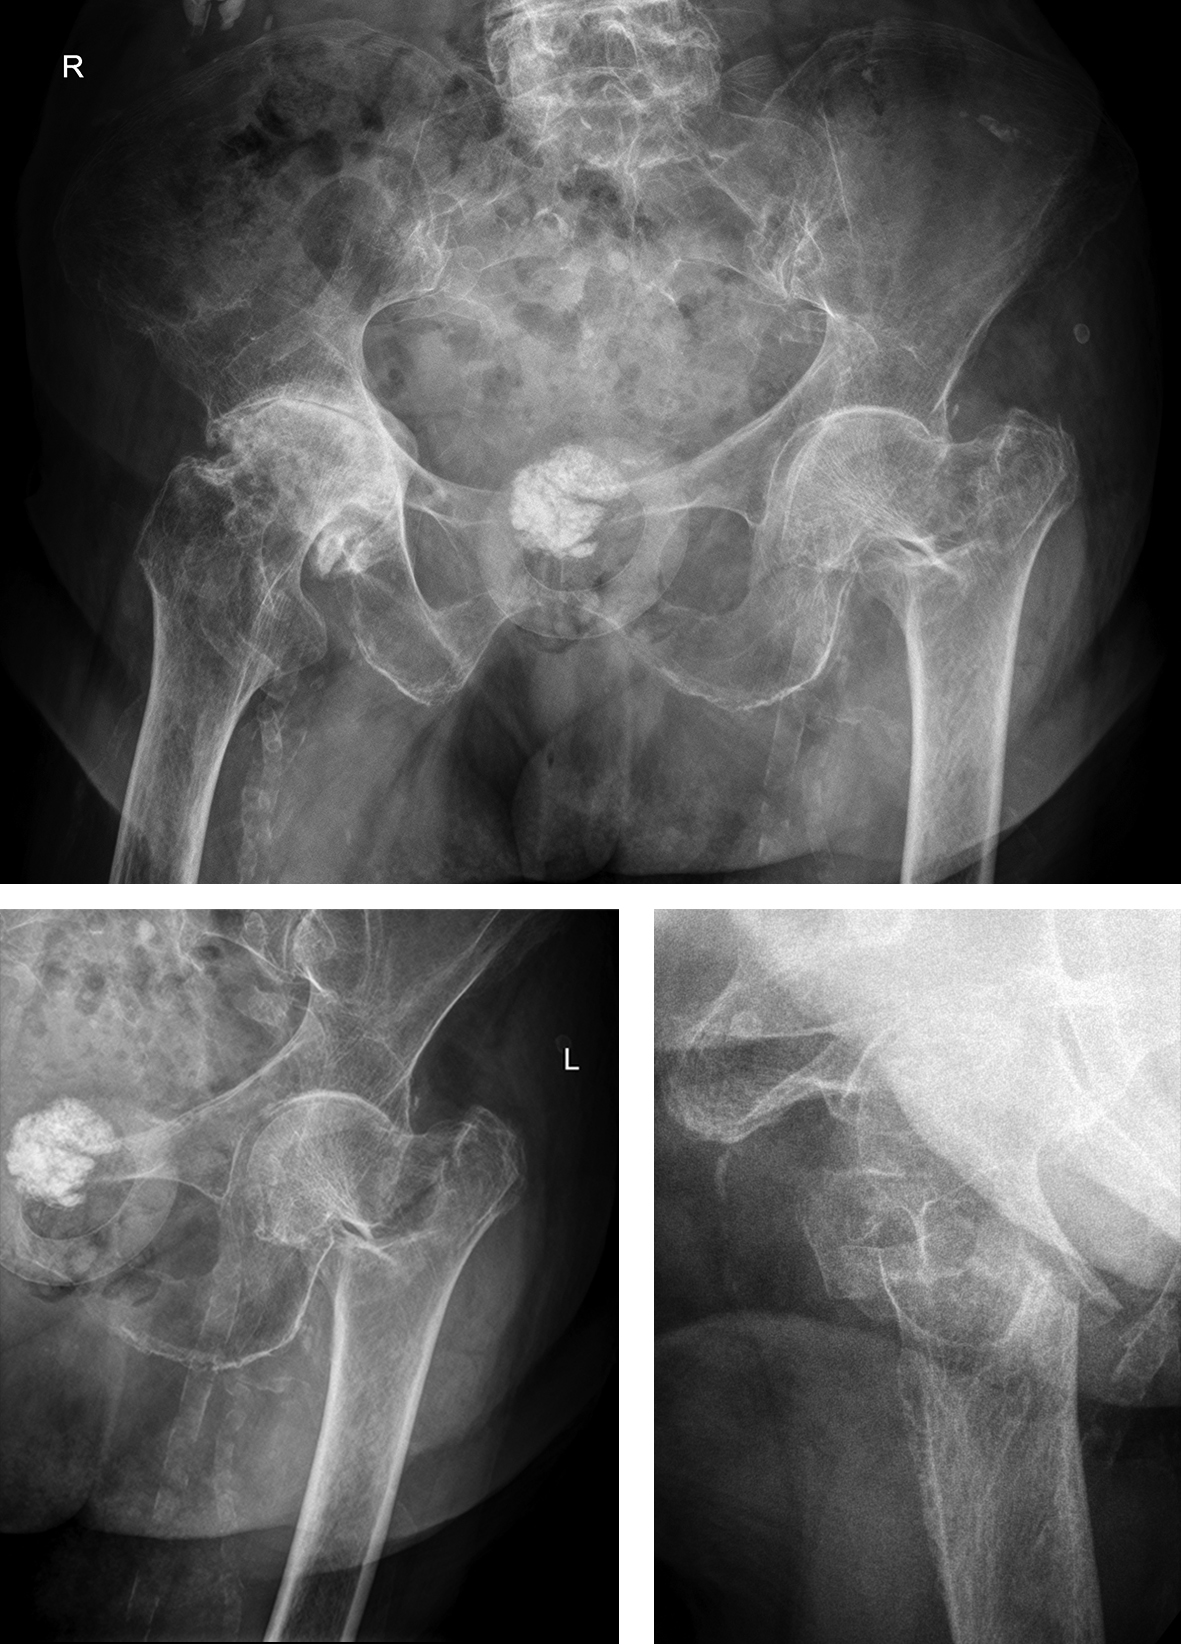

A 98-year-old female patient sustained a pertrochanteric fracture of the left proximal femur due to fall in her nursing home (Fig 1). There was significant pain and coxarthritis in the right hip, and hypertension. Surgery was performed within 24 hours. There was an indication for augmentation due to the instability of the fracture. The patient additionally suffered from osteoporosis and dementia.